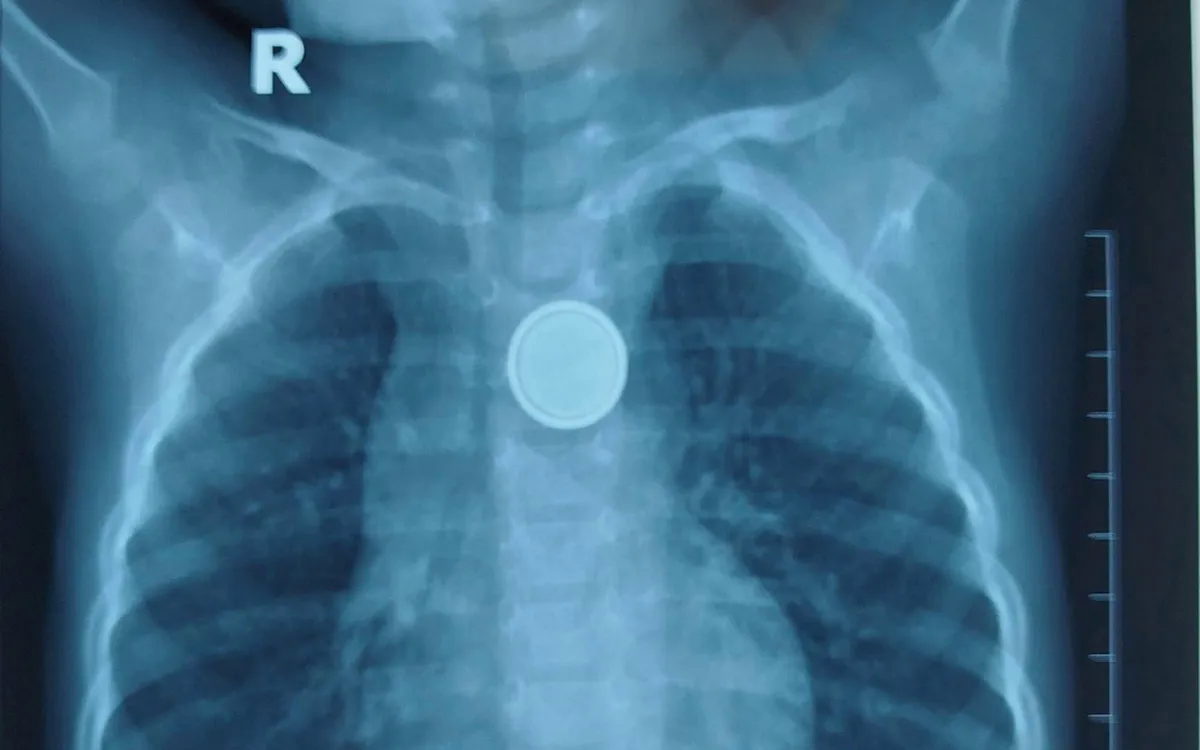

Kết quả X-quang cho thấy dị vật mắc lại ở thực quản. Các bác sĩ tiến hành nội soi cấp cứu và gắp thành công viên pin. Tuy nhiên, quan sát trực tiếp tại vị trí mắc cho thấy vùng thực quản đã bị ăn mòn và loét lớn - minh chứng pin cúc áo có thể gây tổn thương nặng nề chỉ trong thời gian rất ngắn, dù trẻ được đưa đến viện sớm.